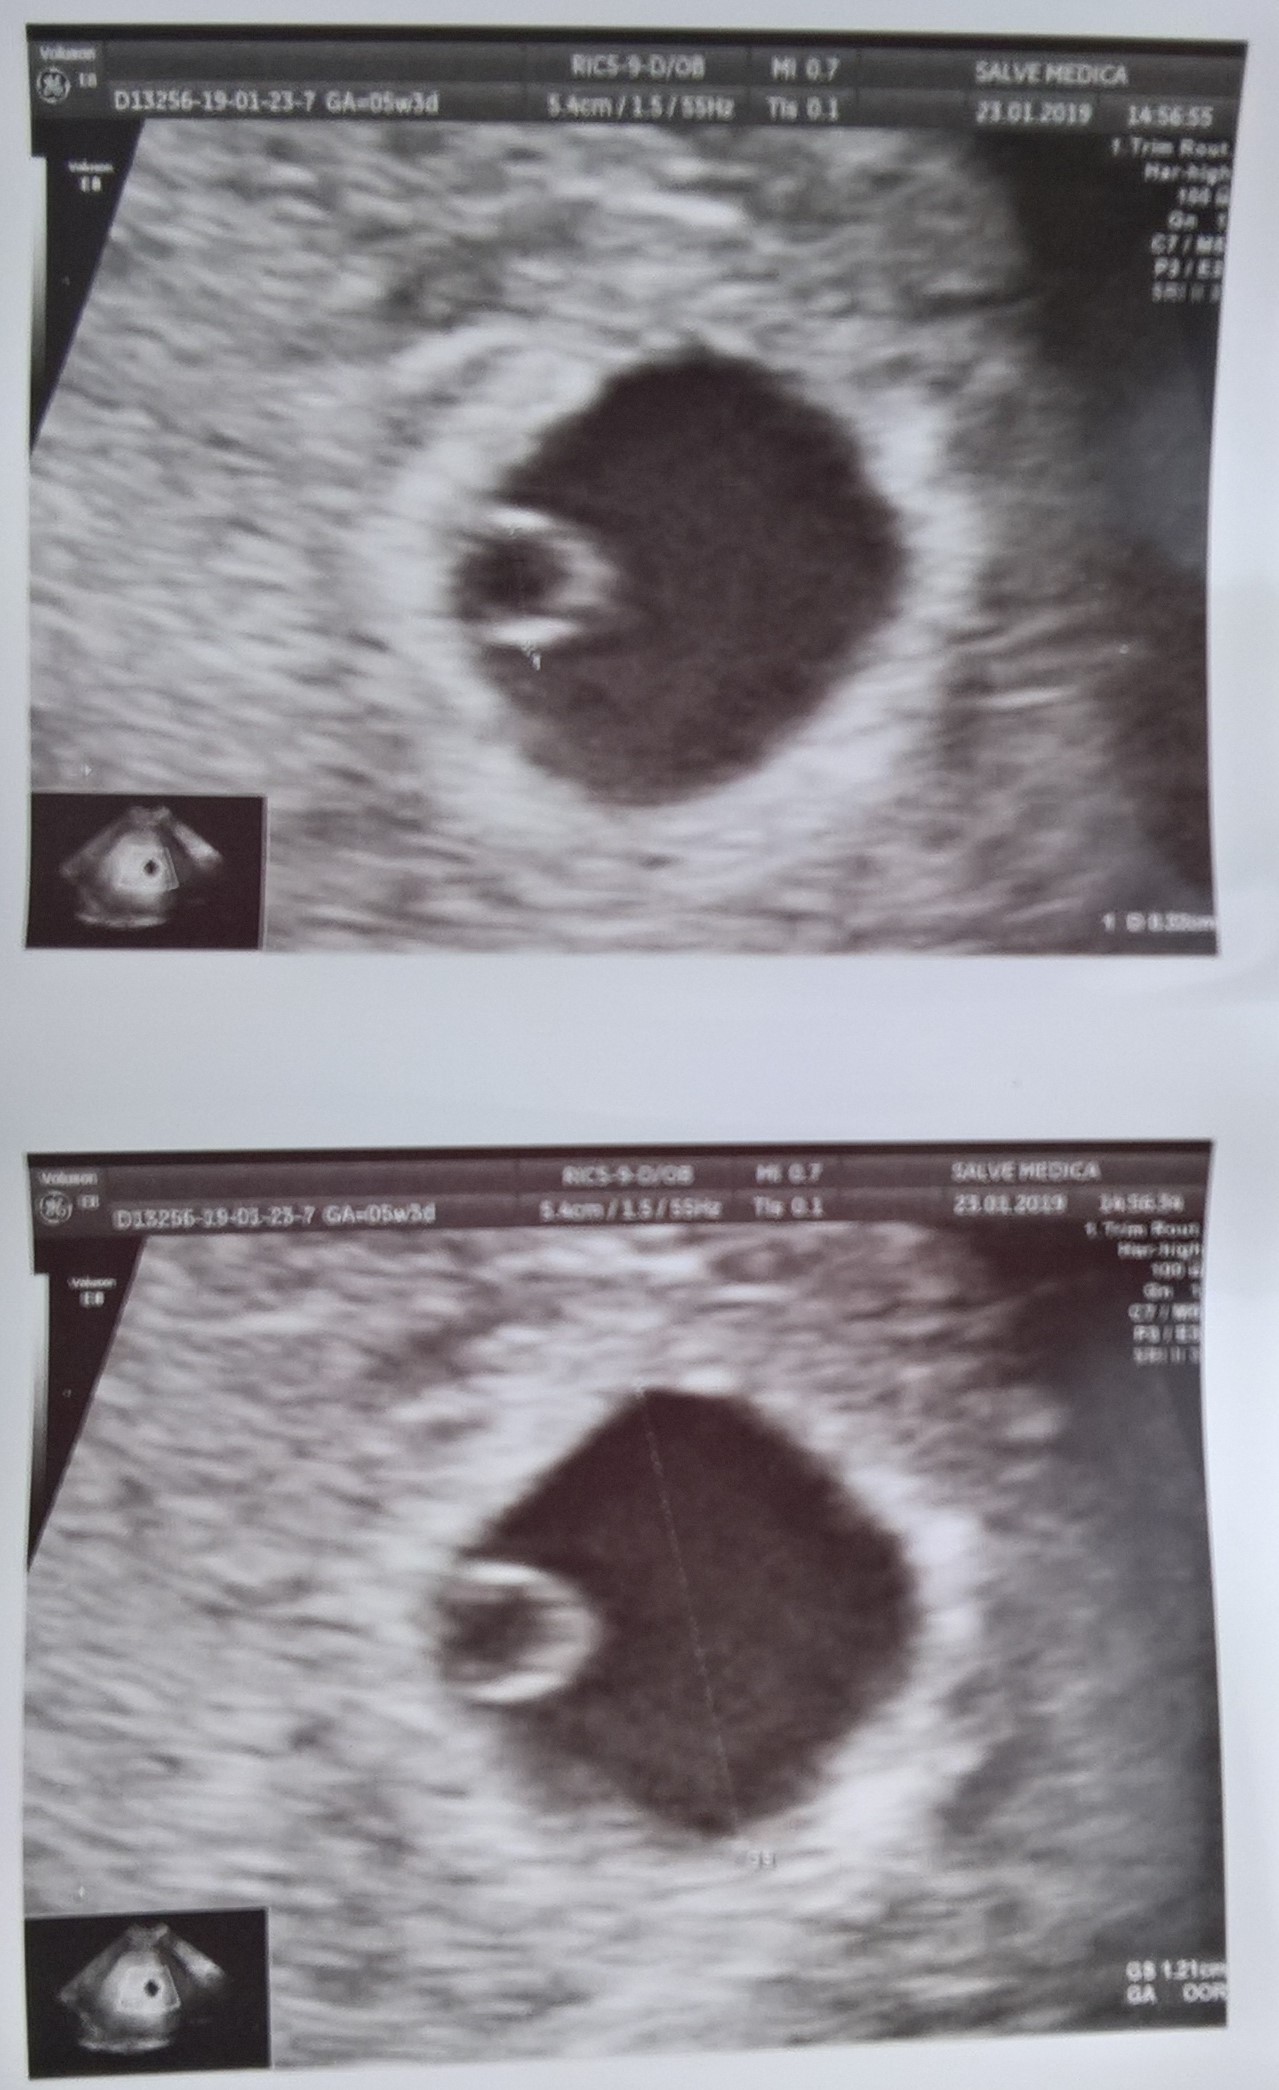

Witam wrześniowe mamy.

W tą środę miałam pierwsze USG. to moja pierwsza ciąża. Orientacyjny termin 22.09

Zobacz załącznik 937453